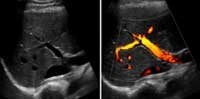

A Doppler ultrasound study may be part of an ultrasound examination.

Doppler ultrasound is a special ultrasound technique that evaluates blood flow through a blood vessel, including the body's major arteries and veins in the abdomen, arms, legs and neck.

• Color Doppler uses a computer to convert Doppler measurements into an array of colors to visualize the speed and direction of blood flow through a blood vessel.

Doppler ultrasound, a special application of ultrasound, measures the direction and speed of blood cells as they move through vessels. The movement of blood cells causes a change in pitch of the reflected sound waves (called the Doppler effect). A computer collects and processes the sounds and creates graphs or color pictures that represent the flow of blood through the blood vessels.